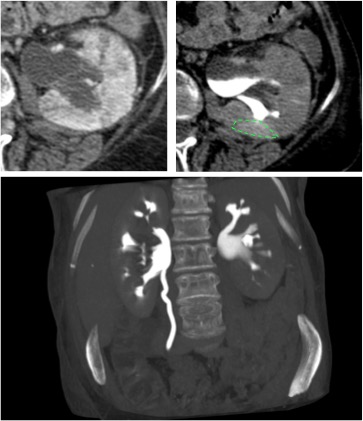

Se procede a realizar TC abdomino-pélvico con contraste en fase nefrográfica y excretora:

Conclusión: se nos presentó un caso de un paciente con una sospecha de infección renal complicada ya que tras cuatro días de tratamiento antibiótico no hubo mejoría. Ante los hallazgos observados en TC, podemos establecer el diagnóstico de pieloureteritis renal izquierda con signos de hidroureteronefrosis leve hasta vejiga.

B- Con el TCMD con contraste en fase excretora podemos estudiar las vías de manera más prescisa y hacer reconstrucciones. Estudio normal.

C- UIV de una hidroureteronefrosis izquierda leve (grado II/IV) hasta vejiga.